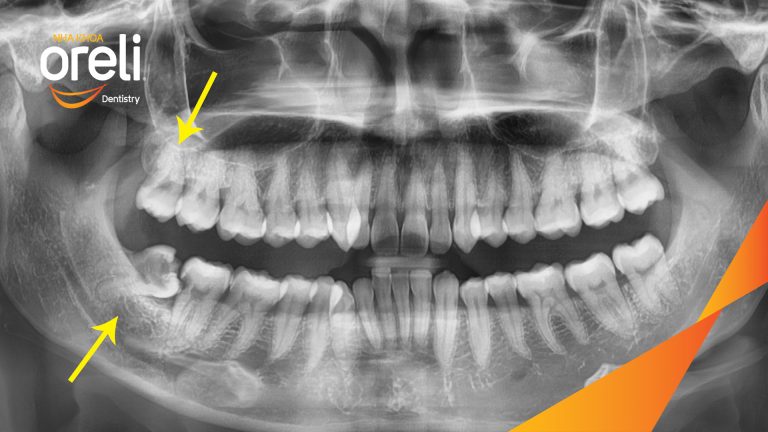

Nhổ răng khôn hàm dưới – Case tại Oreli Buôn Ma Thuột

Nhổ răng khôn

Mọc lệch